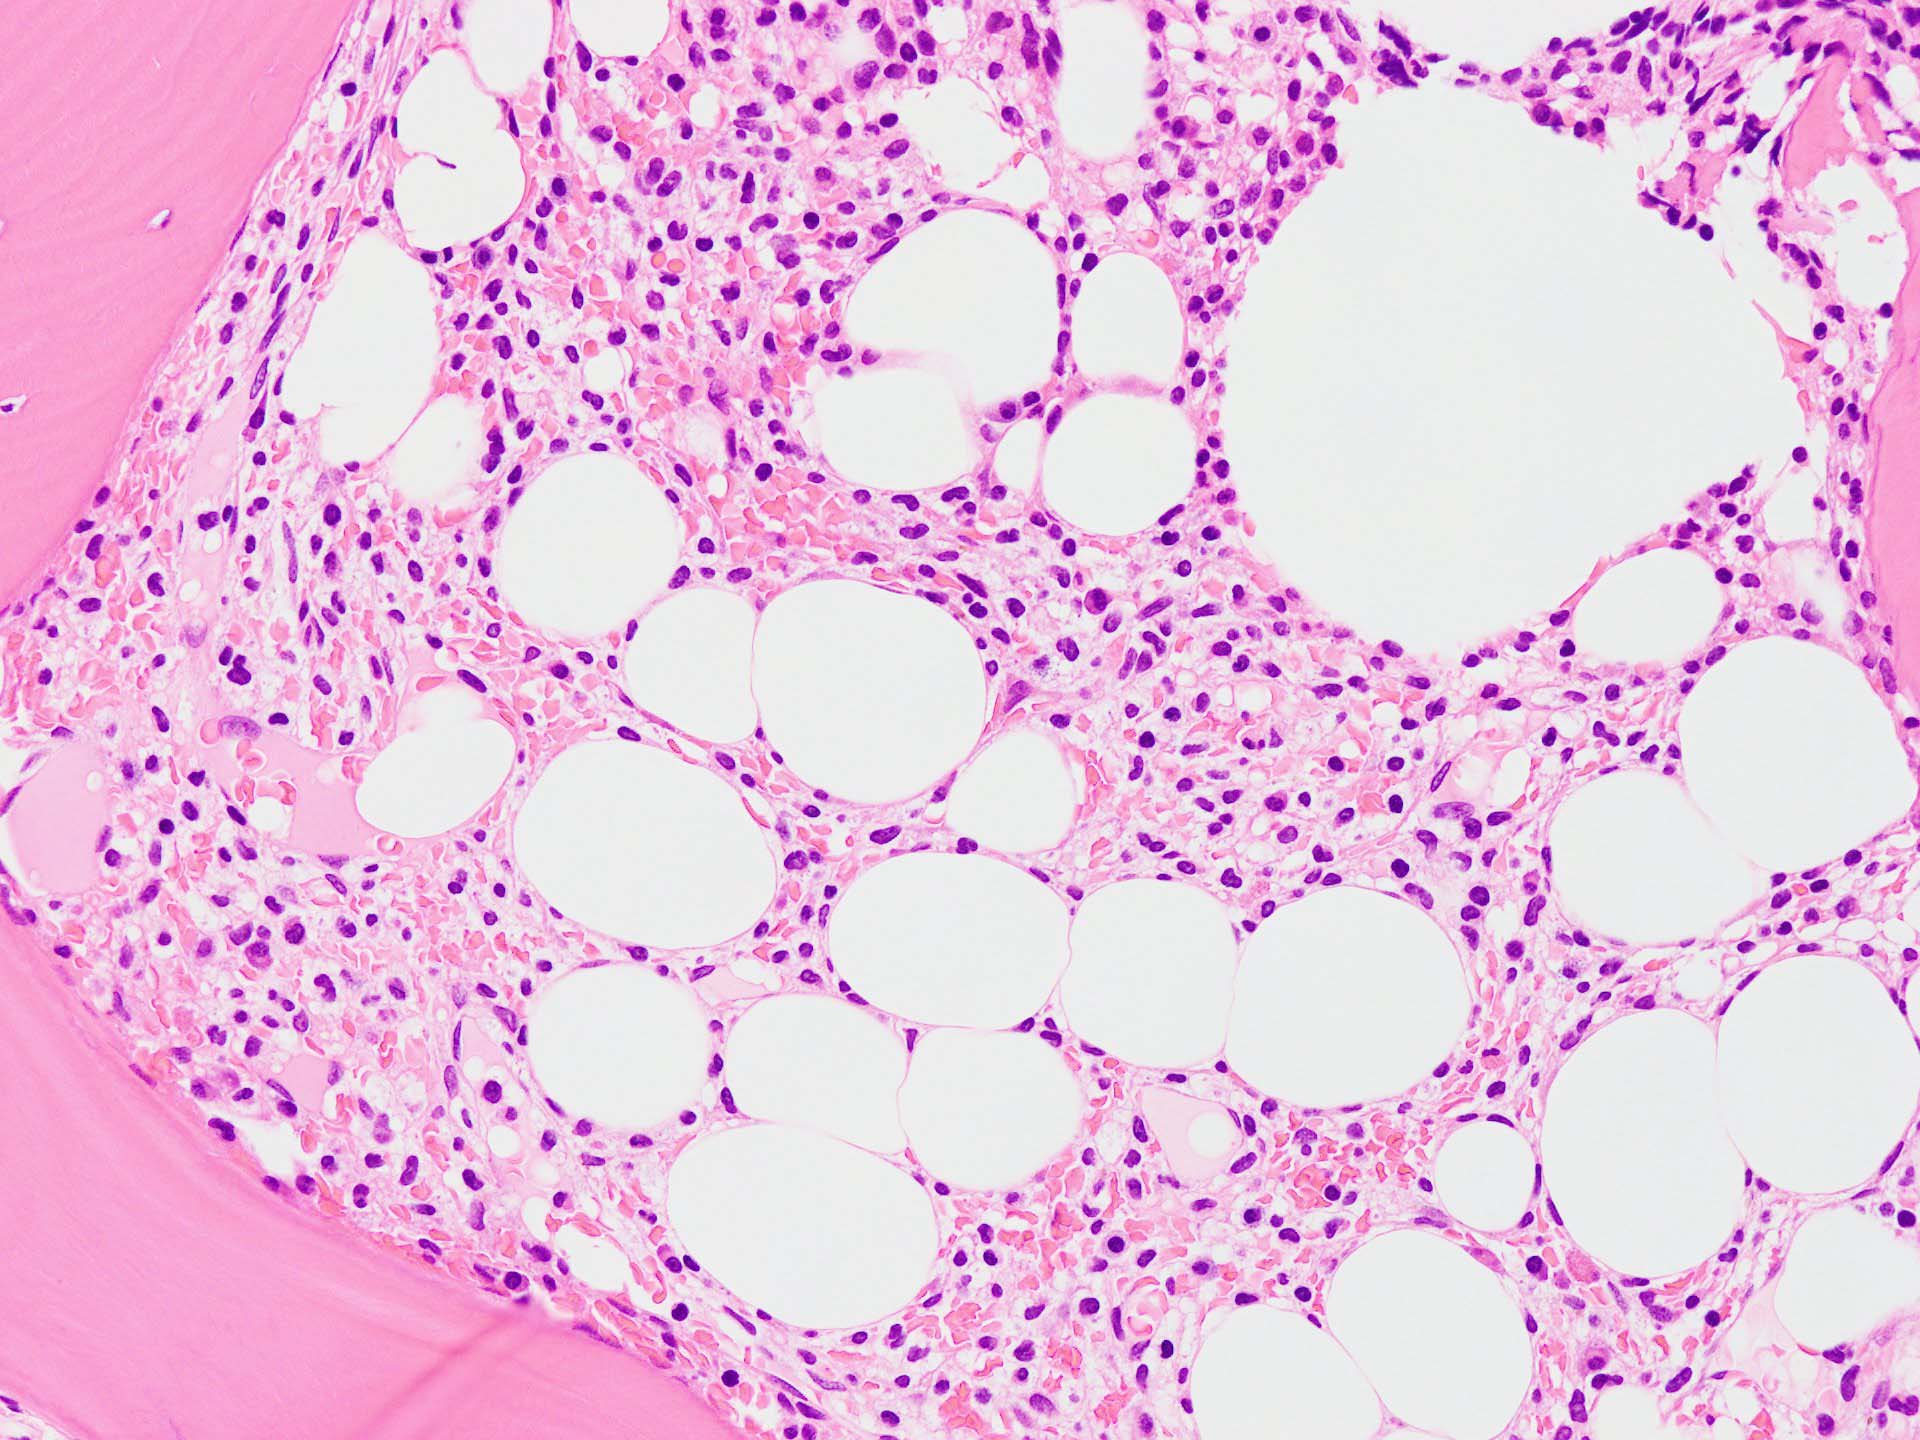

bone marrow trephine biopsy: dry tapのため骨髄生検が行われる. cellularityは40-80%とhypercellular marrow. 流れのある細胞配列は線維化を疑わせる.

ASD-Giemsa陰性の細胞がシート状に増殖する. 核はクロマチン濃染, 核小体は不明瞭.類円形, 卵円形, くびれを持つ多稜形核, 長円形いびつで屈曲した核, など多彩. 細胞質は淡清色調, 広く淡明. 赤芽球血島は幼若赤芽球のみで形成される異形成像を示す. やや離れて成熟赤芽球が疎な集簇を示す.

Ag染色では, 疎な弾性線維が増生し,増殖細胞を小胞巣状に分画するいわゆる「lymphomatoid pattern」を呈する. 本例では, Mgkに異形成所見がある.